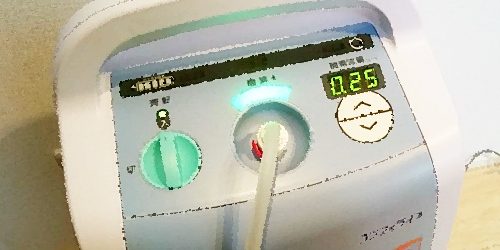

本記事では、在宅酸素療法(HOT)について綴っています。 慢性肺疾患のお話:ミニ太成長記録03:慢性肺疾患 慢性肺疾患に関わる呼吸…

慢性肺疾患のお話:ミニ太成長記録03:慢性肺疾患 慢性肺疾患に関わる呼吸管理のお話1(口の人工呼吸器について):ミニ太成長記録05…

赤ちゃんの肺の機能は妊娠32週前後で完成・成熟するため、それより前に誕生した赤ちゃんは肺の機能だけでなく自発呼吸・血液の循環などが…